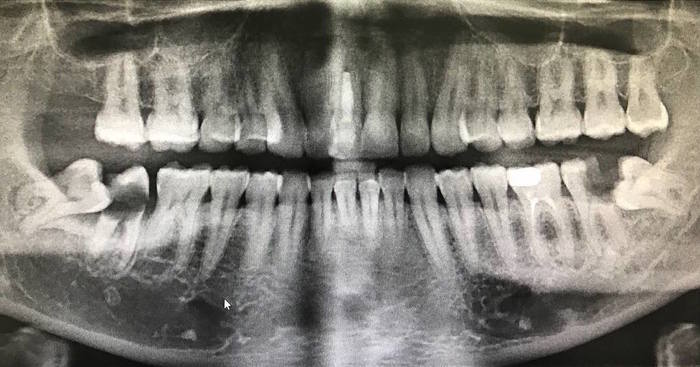

Вот наглядный пример такого того, к чему может привести несвоевременное удаление зуба мудрости. И не болит же! Мужчина обратился совсем с другой проблемой, обнаружили случайно, когда сделали панорамный снимок зубов.

Из-за неправильного положения 8ки на контактной поверхности зуба номер 7, образовалась достаточно глубокая кариозная полость, уходящая глубоко под десну.

Как вы думаете, с чем пациент обратился? Нет, не с дикой болью или отеком, как многие могли подумать. А вот с чем — «Чет у меня еда забивается снизу справа, посмотрите.» То есть молодого человека беспокоит лишь то, что забивается еда… просто забивается еда, Карл! На вопрос, а болело ли? Ответ — «Да нет, никогда не болело и ничего не беспокоило.» Ну… порядок действий в этом случае вы уже знаете. Вот вам и — «подожду, пока не забеспокоит».

Если вы думаете, что это самое страшное, что может вас ожидать, как бы не так.